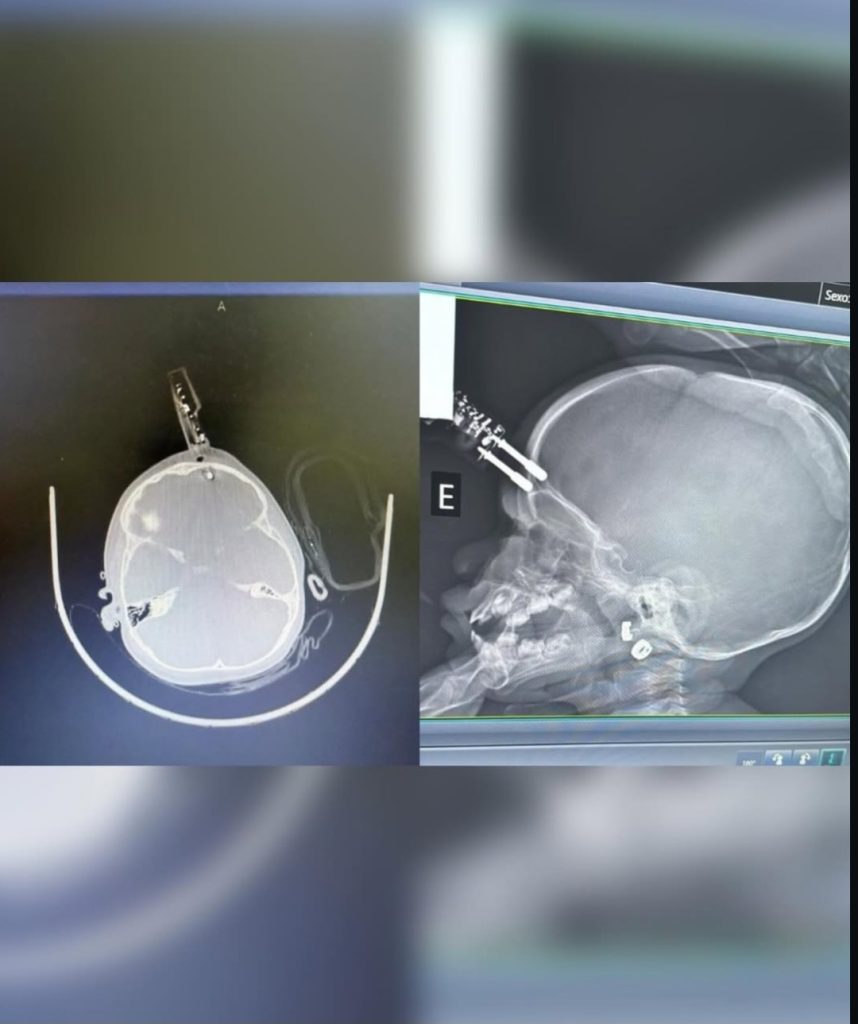

A principal hipótese levantada pela equipe médica é de que a criança estava com o objeto nas mãos no momento da queda. Imagens do caso mostram que o carregador perfurou o crânio na região frontal, próximo ao olho. De acordo com informações preliminares, a mãe da bebê havia ido ao banheiro quando o acidente ocorreu.

No hospital, a criança foi encaminhada imediatamente ao centro cirúrgico, onde passou por um procedimento para a retirada do objeto e reconstrução da área atingida. O quadro clínico é considerado estável, e a paciente segue sob acompanhamento médico.